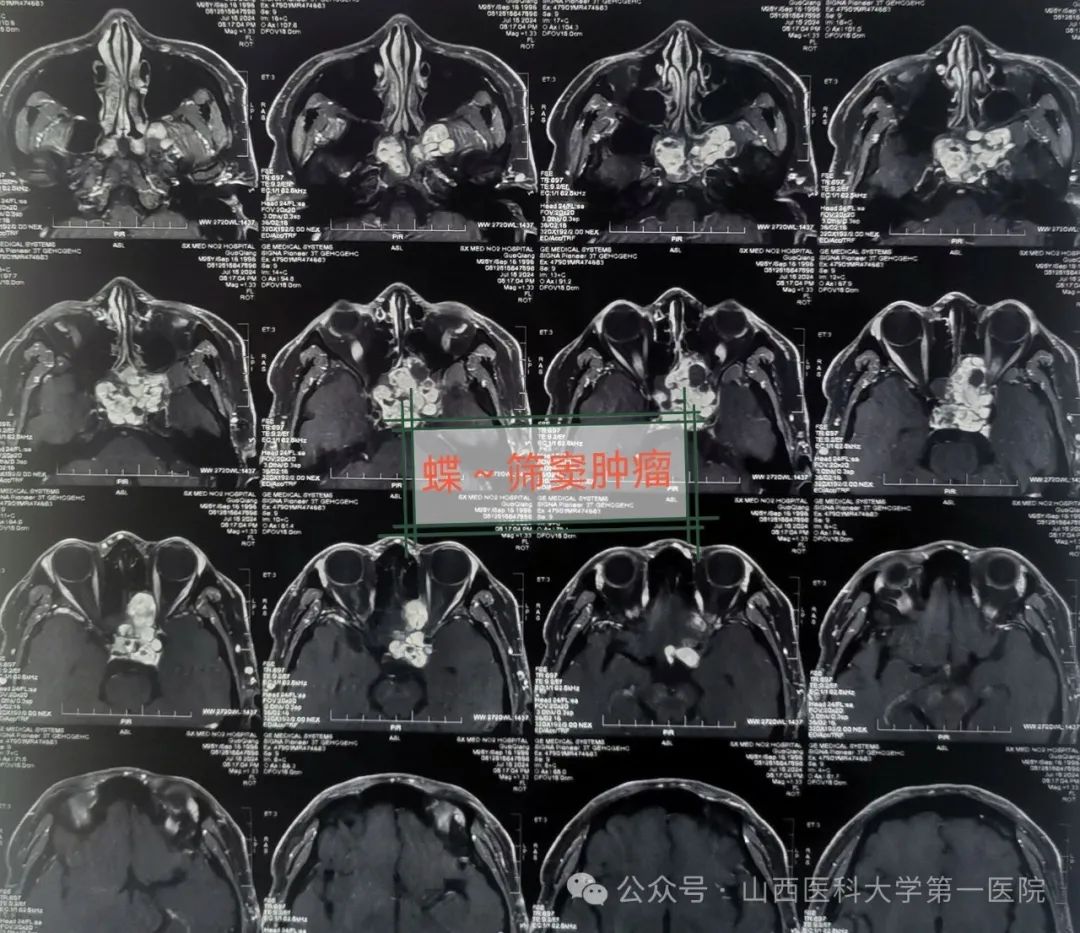

医生通过检查发现郭某一侧眼球明显向前外方突出,眼球活动有受限,视力处于急剧下降状态,鼻窦冠状位CT与MRI提示:蝶-筛窦内充满混杂密度肿物阴影,眼眶中颅底受压,考虑鼻窦占位性病变而引起。近日在全麻下行鼻内镜鼻窦肿瘤涉眶与颅底根治切除手术,由耳鼻咽喉-头颈外科皇甫辉教授主刀,术中显露术野、暴露病变组织,发现病变位居单侧鼻腔筛窦与蝶窦,已侵犯单侧眼眶及球后以及中颅底,病变范围广,内镜下切除鼻腔筛窦与蝶窦病变组织,开放蝶窦,肿瘤侵犯眼眶后、海绵窦被侵犯,暴露颈动脉管、颈内动脉视神经隐窝以及视神经管得以保护,同时做视神经减压,最终完整切除肿瘤,手术获圆满成功。